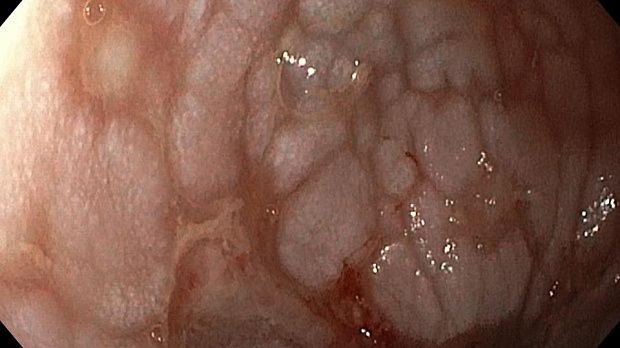

Публикации из социальных сетей: “Cobblestone esophagitis” (эзофагит со слизистой булыжной мостовой)

“Cobblestone esophagitis” (эзофагит со слизистой булыжной мостовой) - редкая эндоскопическая находка и ассоциируется с эозинофильным эзофагитом, кандидозом и пищеводом Барретта у взрослых. Он также может быть найден при тяжелом рефлюкс-эзофагите, вторичен к дистальной обструкции гастроинтестинального тракта. В нашем случае - это пациент после с 9-летним стажем бандажирования кардиального отдела желудка, признаками дуоденостаза, фундальной эрозивной гастропатией, расширением пищевода и уровнем жидкости в нем при горизонтальном положении, грыжи ПОД, эрозивно-язвенном дистальном эзофагите.. Пациент просто пришел удалить полип в прямой кишке и заодно посмотреть, что творится в желудке.... Ацетообеление+NBI+биопсия. ИПП на 3-4 мес и повтор для решения о Барретте.